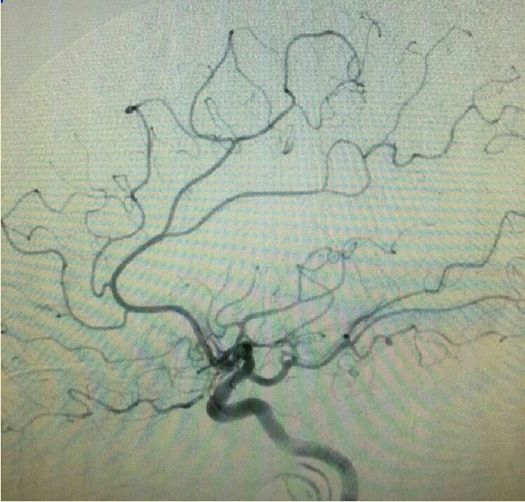

药物治疗无效症状进行性加重,拟行球囊扩张+支架成形术。微导管过狭窄后超选即见血流被完全阻断。

行球囊(gateway1.5*9)扩张:

支架(Solitaire 4.0*20)到位尚未打开: